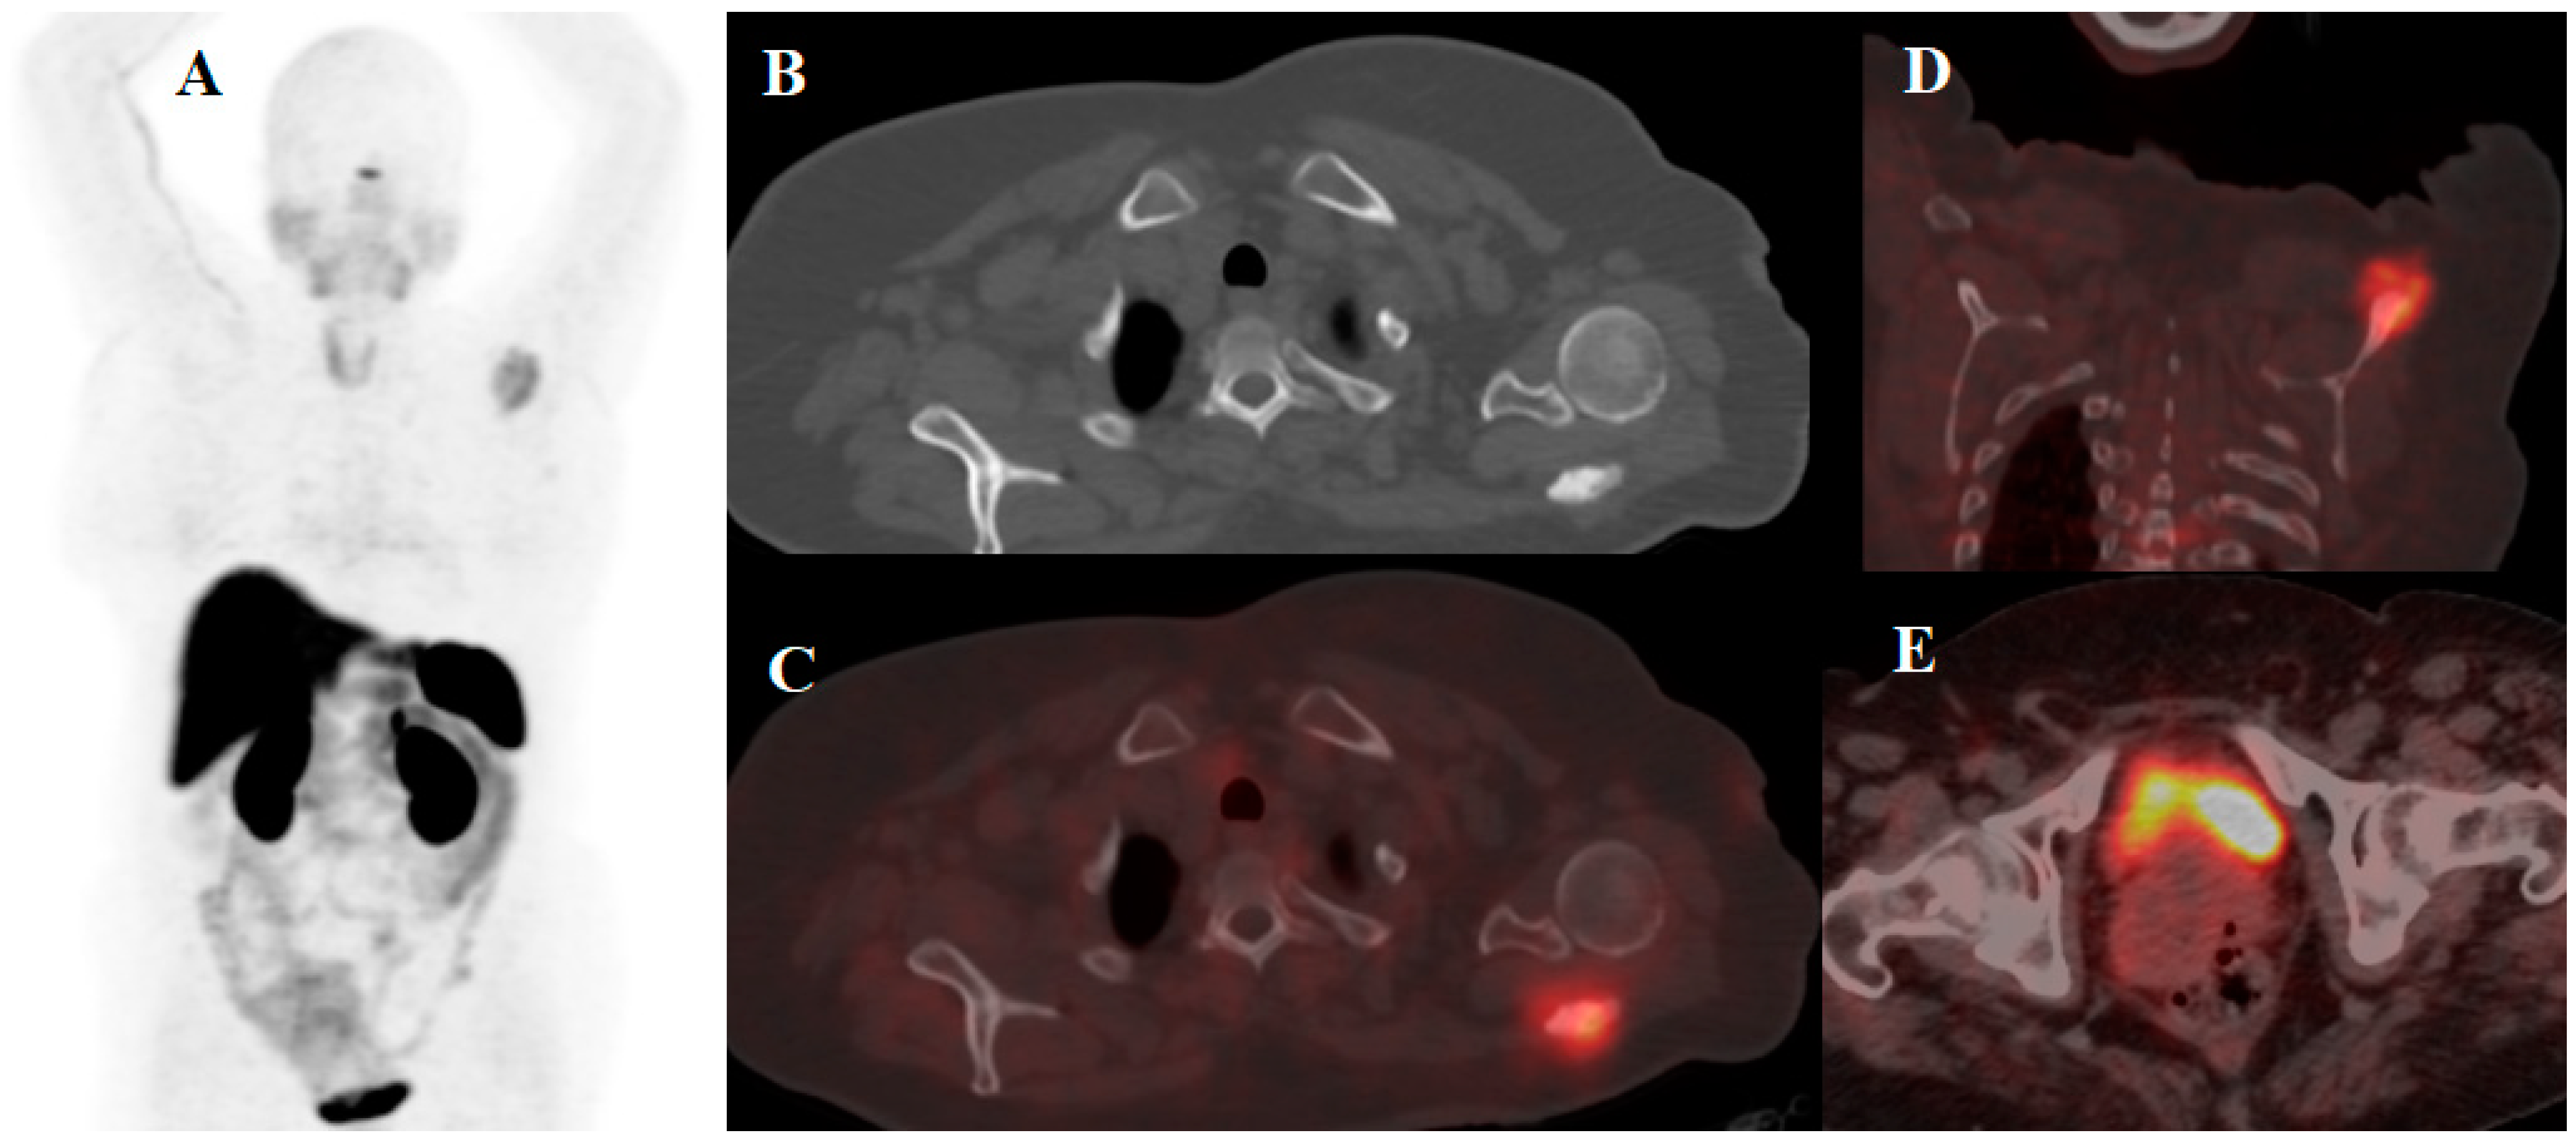

- Mirzaei, S.; Revheim, M.-E.; Raynor, W.; Zehetner, W.; Knoll, P.; Zandieh, S.; Alavi, A. 64Cu-DOTATOC PET-CT in patients with neuroendocrine tumors. Oncol. Ther. 2020, 8, 125–131. [Google Scholar] [CrossRef]

- Pfeifer, A.; Knigge, U.; Mortensen, J.; Oturai, P.; Berthelsen, A.K.; Loft, A.; Binderup, T.; Rasmussen, P.; Elema, D.; Klausen, T.L. Clinical PET of neuroendocrine tumors using 64Cu-DOTATATE: First-in-humans study. J. Nucl. Med. 2012, 53, 1207–1215. [Google Scholar] [CrossRef]

| [64Cu]Cu-DOTA-TOC | NET | 33 | 2019 | High detection rate and high target to background ratio in images raised [64Cu]Cu- DOTA-TATE as a promising and safe radiolabeled SST derivative for NET detection | [22] |